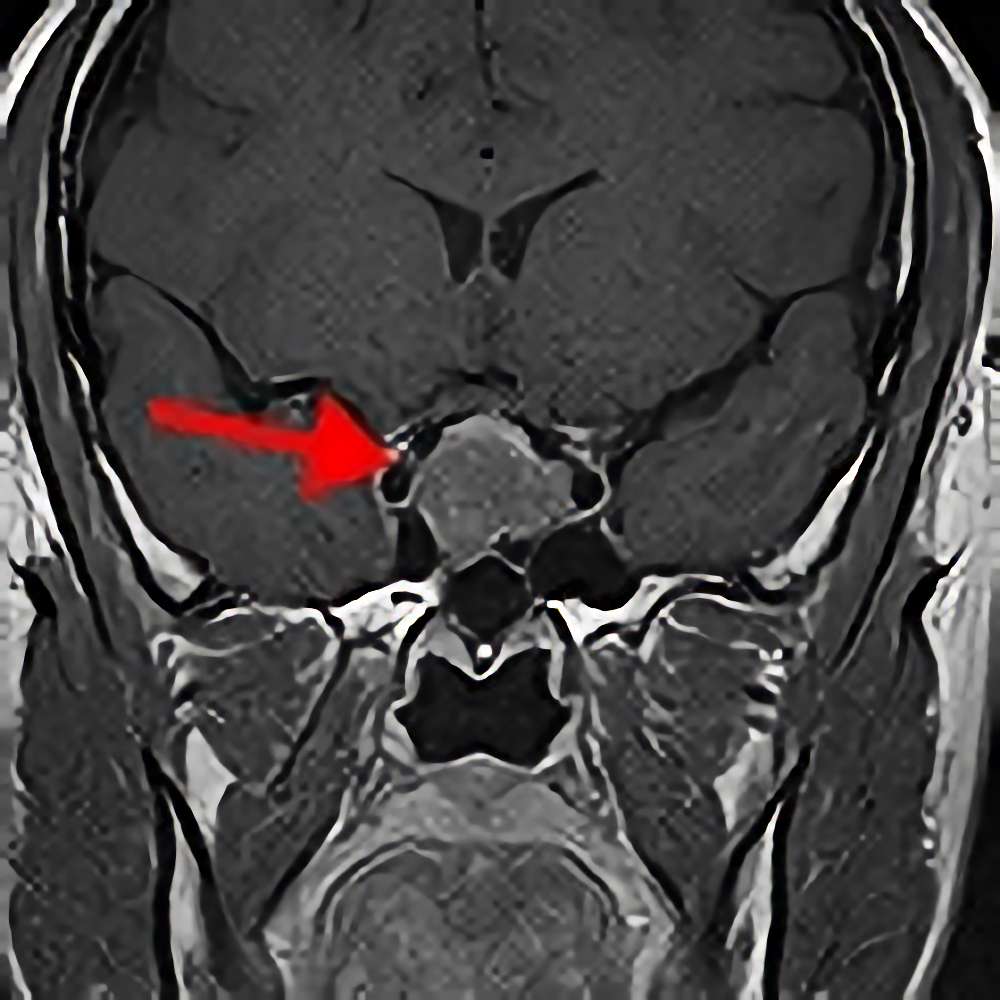

'13年12月

60代

下垂体腺腫

No.’13_190 手術前1

No.’13_190 摘出 前

No.’13_190 摘出 後